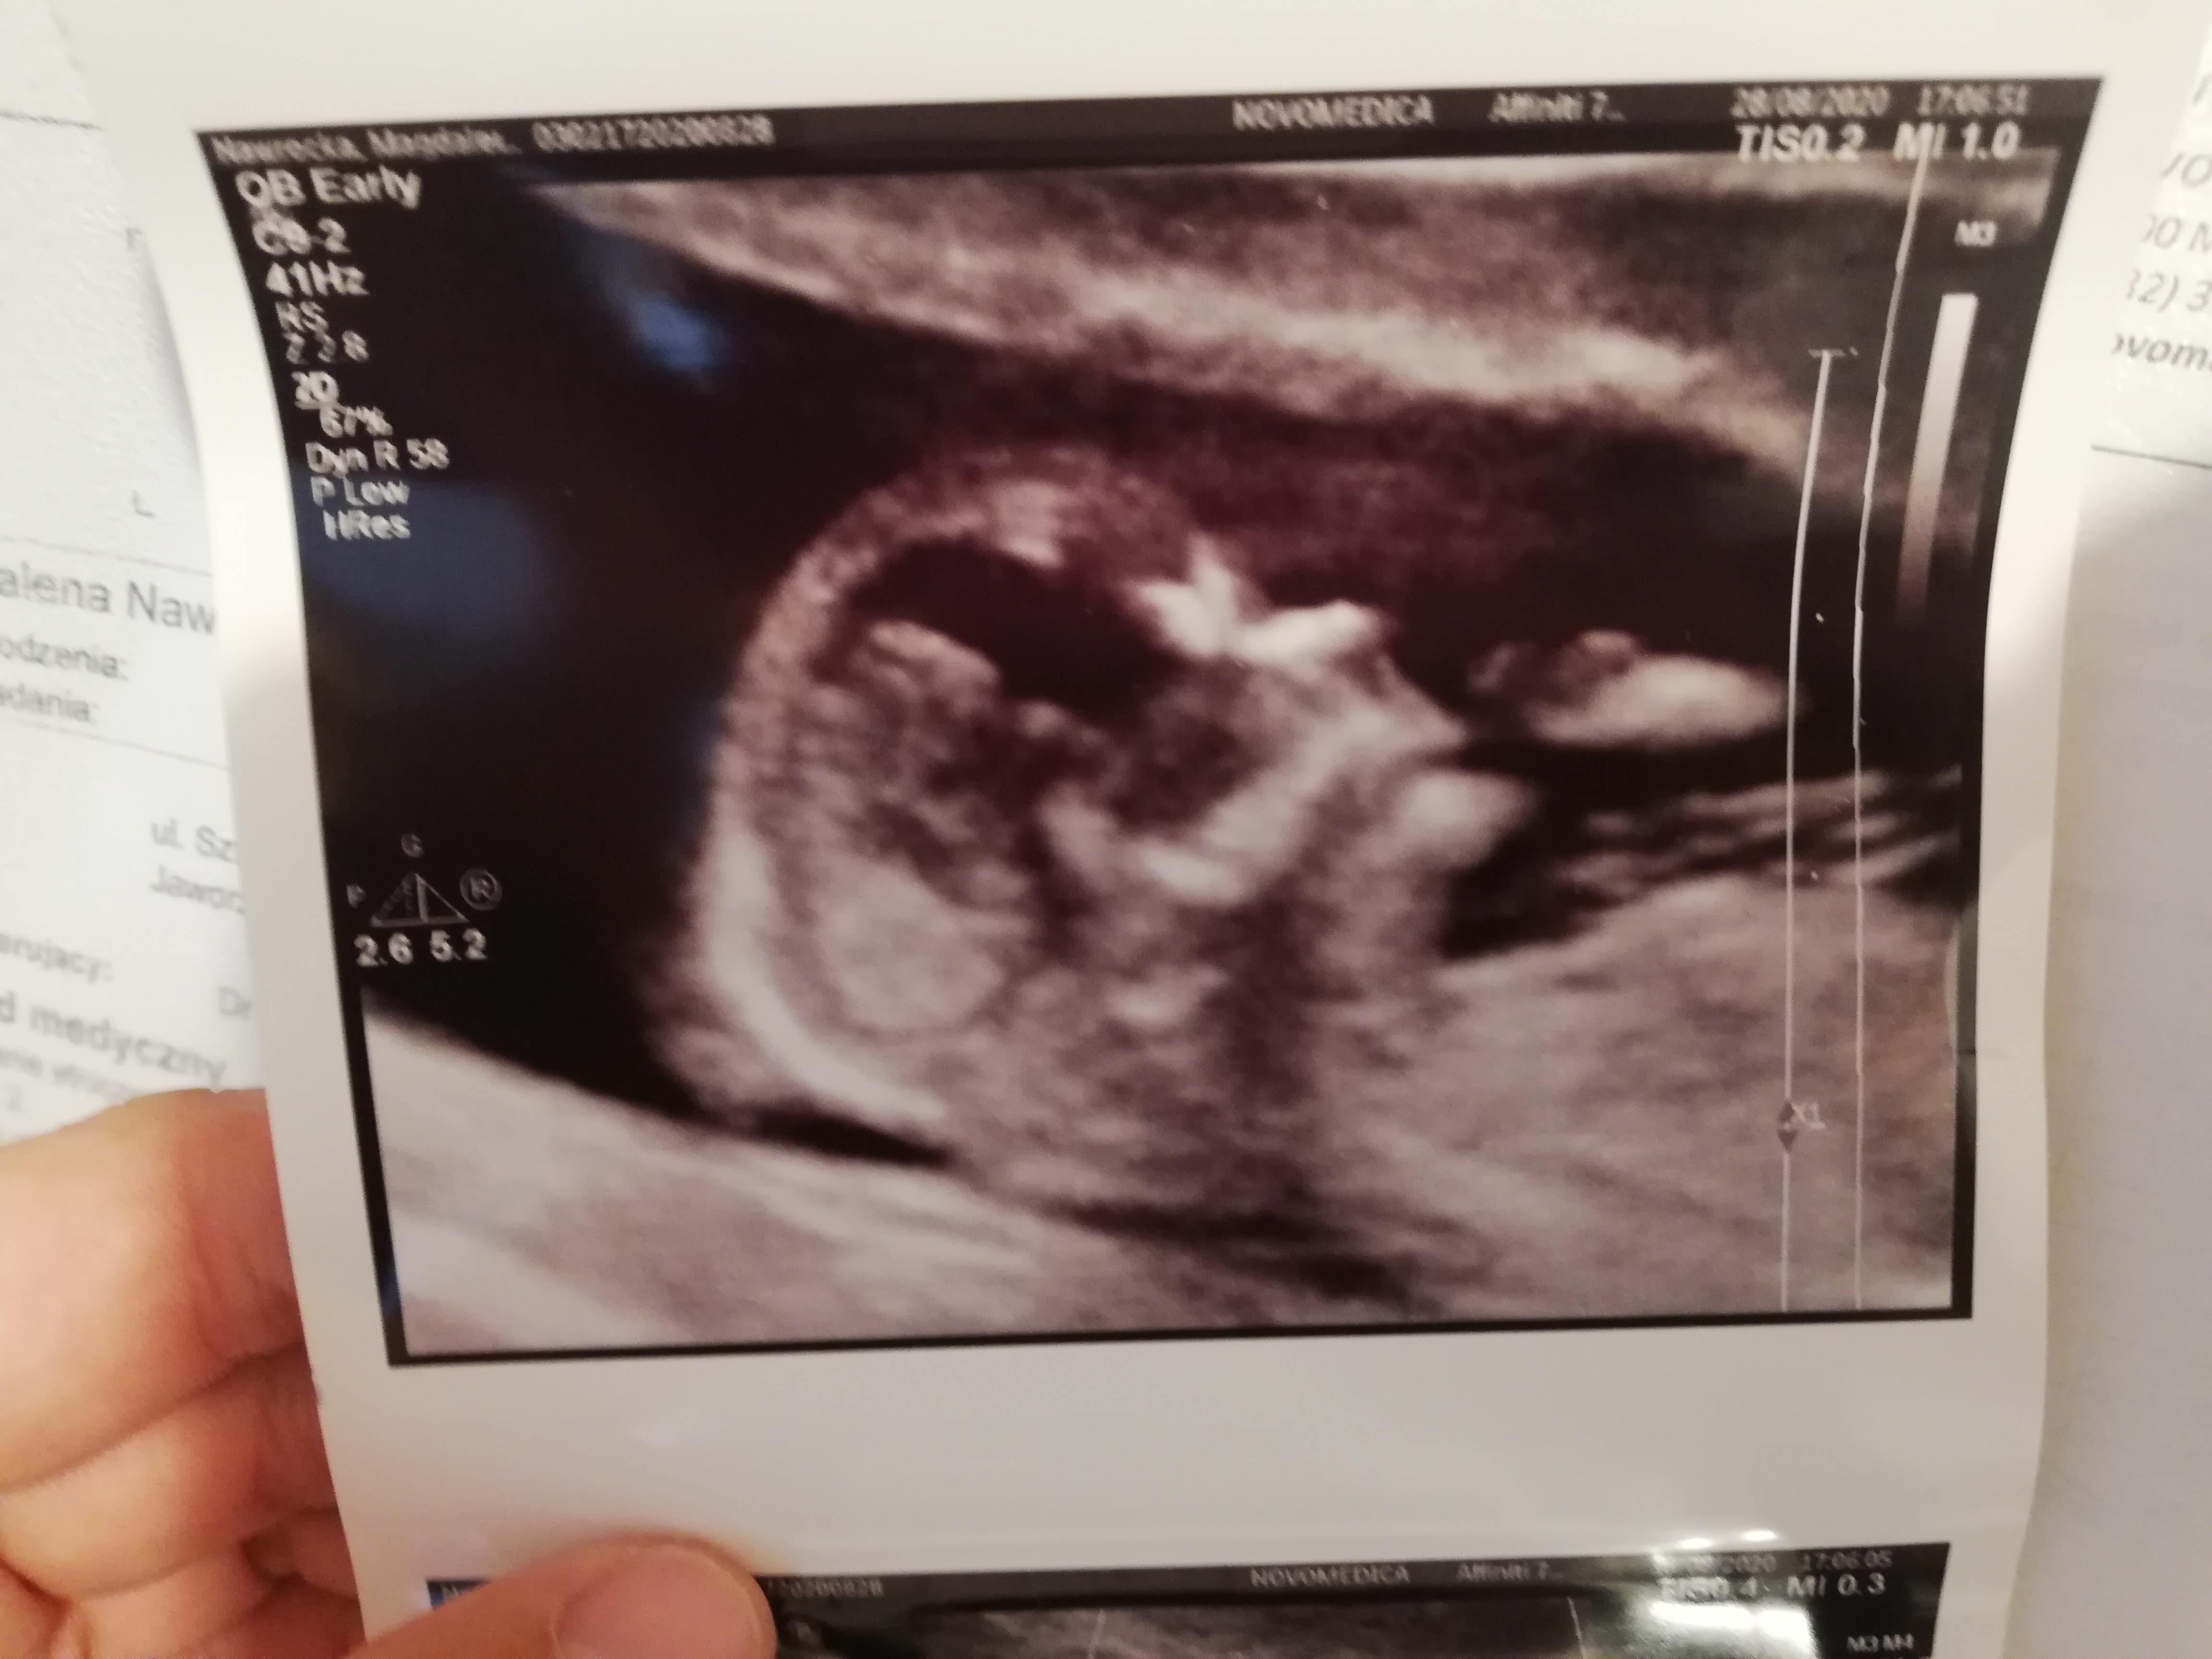

My jak zwykle ssiemy kciuka 😂 niestety dużo leżeć mało dźwigać ciężko przy dwójce dzieci mam nisko łożysko i dostałam duphaston

• IMG_20200828_184427.jpg

IMG_20200828_184427.jpg

1,7 MB · Wyświetleń: 102